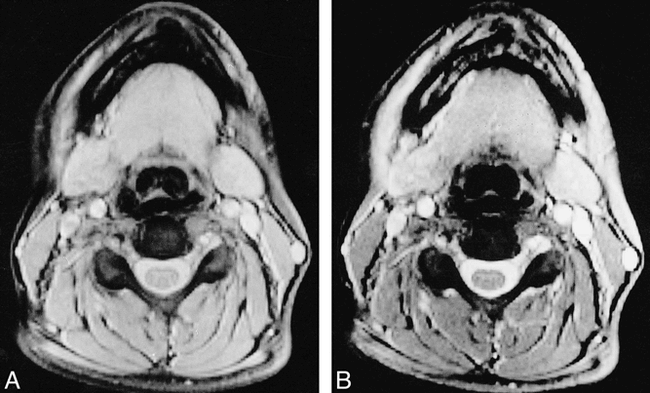

MR scans were obtained from all the patients and volunteers by using a 1.5-T system. With a tailored cervical spine phased-array coil for signal reception, we obtained two sets of two-dimensional gradient-echo sequences (640/10/2 [TR/TE/excitations], flip angle = 20°) with and without a saturation pulse (the saturation pulse was an off-resonance RF pulse centered 1.5 kHz below the water frequency with a gaussian envelope of 7.68 ms duration and α = 500°). One set consisted of 20 axial, contiguous slices with a thickness equal to 5 mm (FOV = 250 × 250 mm; matrix size = 192 × 256) (Fig 1). The other set consisted of 17 sagittal slices with a thickness equal to 3 mm and an interslice gap equal to 0.3 mm (FOV = 280 × 280 mm; matrix size = 224 × 256) (Fig 2).

Axial gradient-echo (TR/TE/excitations = 640/10/2) images of cervical cord at C5 without (A) and with (B) the saturation pulse.